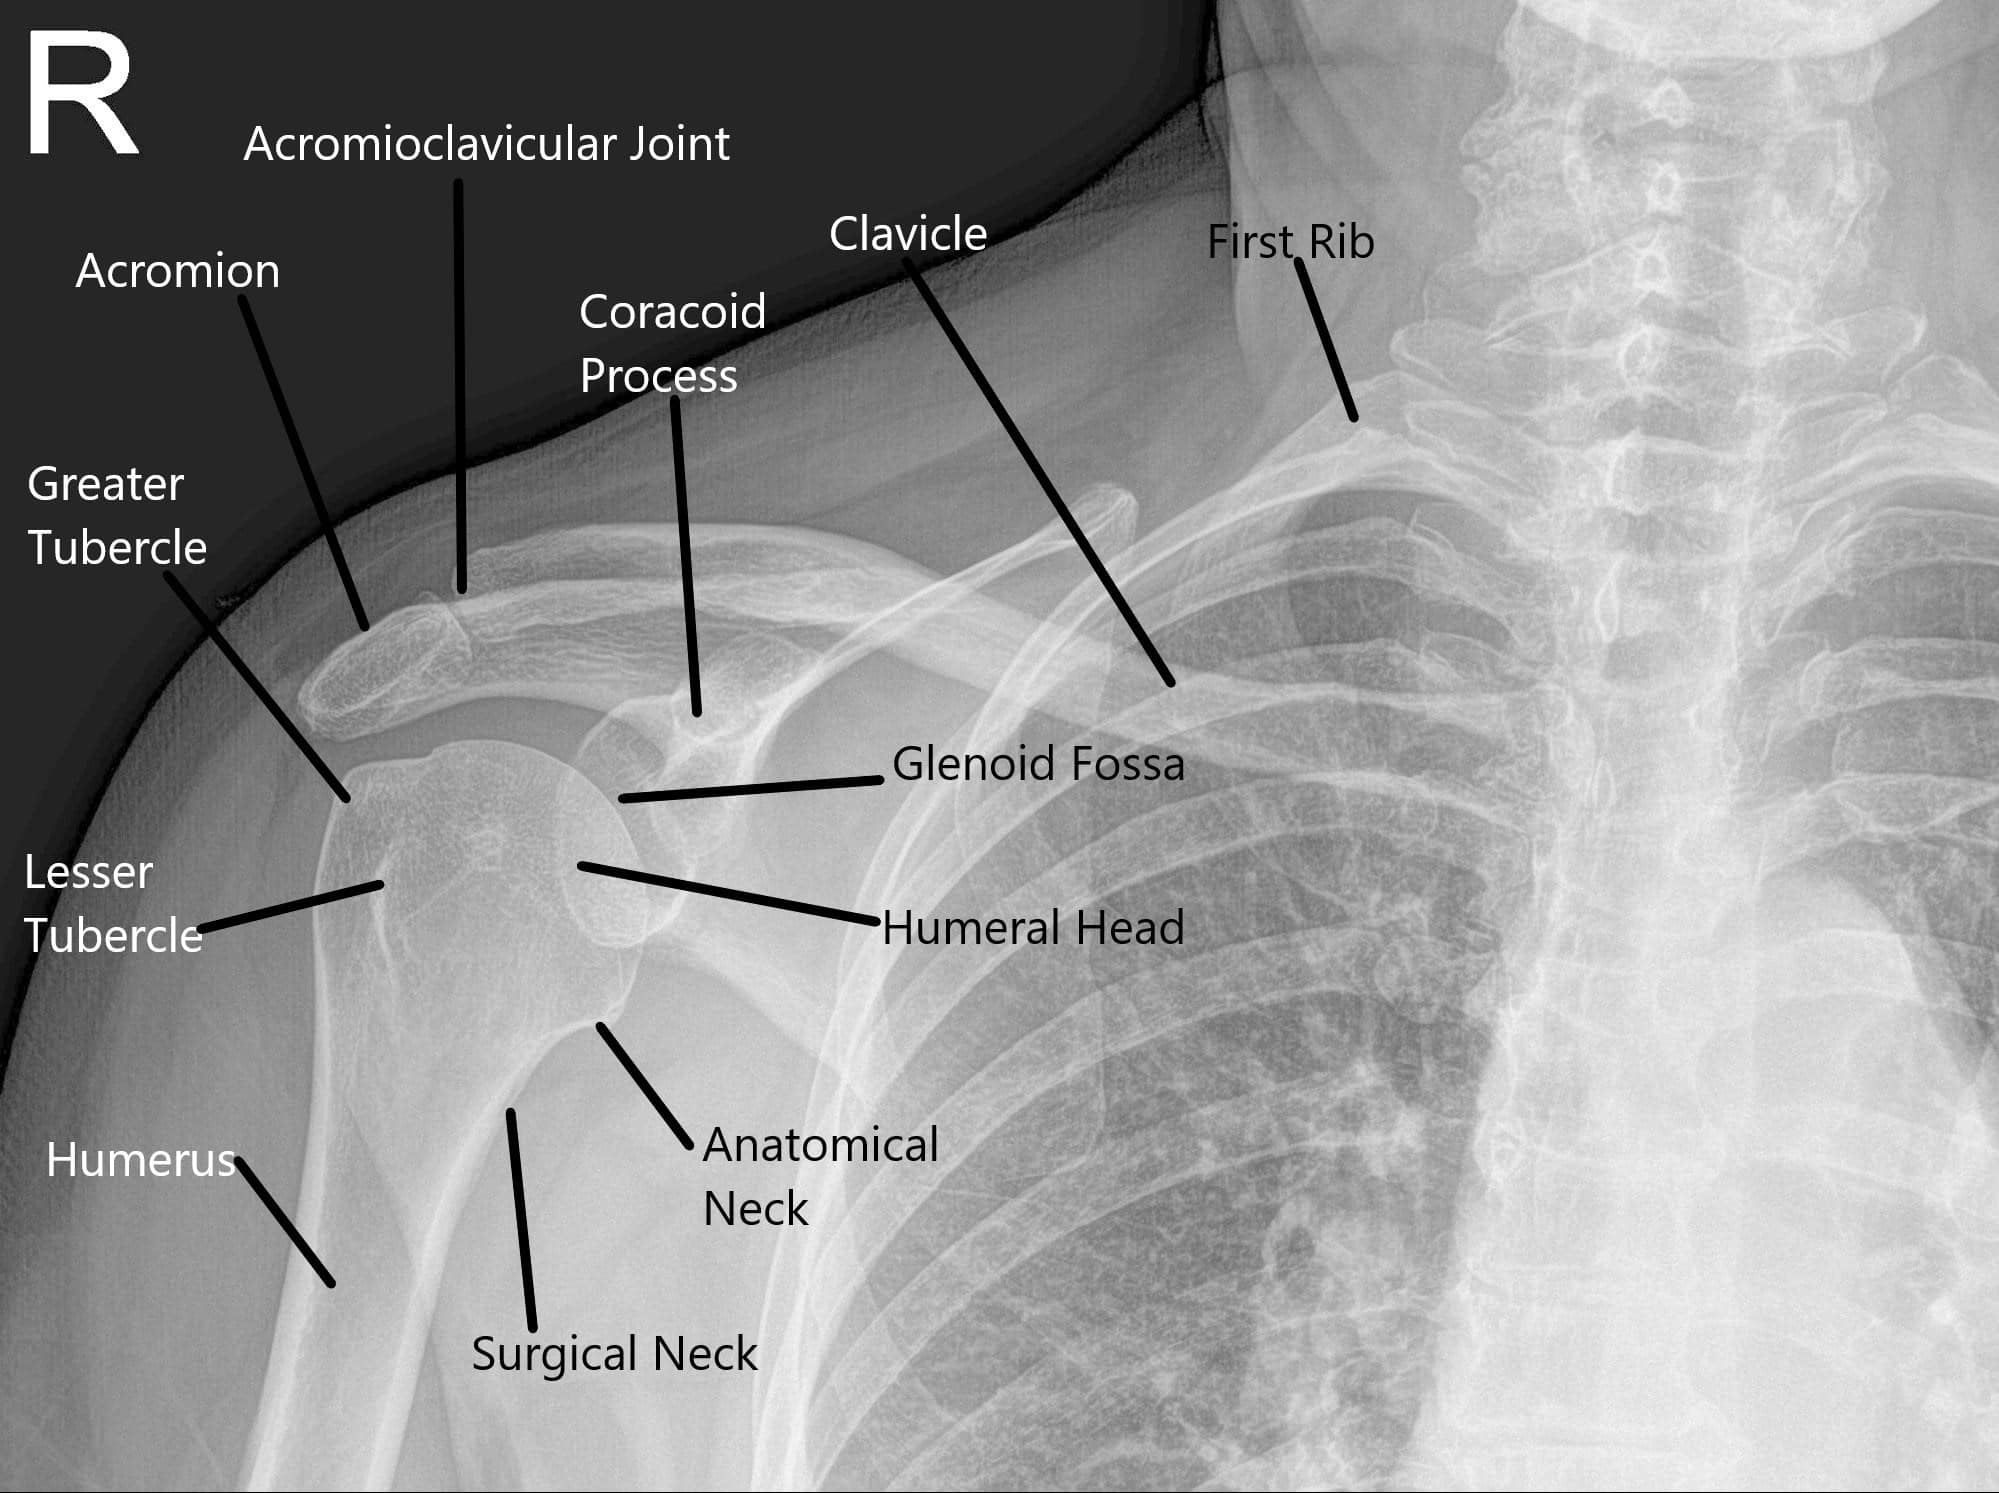

Why Does My Shoulder Keep Coming Out Of Socket . This can cause your shoulder to dislocate, or it may. When the shoulder slips out of place repeatedly, it is called chronic shoulder instability. A dislocated shoulder is when your upper arm bone comes out of place from your shoulder socket. Shoulder instability usually occurs when the lining of the shoulder joint (the capsule), ligaments or labrum become stretched, torn or detached, allowing the ball of the shoulder joint (humeral head) to move. A dislocated shoulder is painful and results in temporary loss of mobility and. A dislocated shoulder occurs when the top part of the upper arm bone partially or fully comes out of the socket. Chronically unstable shoulders can lead to loose shoulder joints that slip out of place. Chronic shoulder instability occurs when the top of your arm bone, also called the head of your arm bone, slips out of its socket. Get medical help as soon as possible if you think. The shoulder is the most mobile joint in the body but also the least stable making the shoulder the most likely joint to dislocate. Shoulder instability occurs when the arm’s ball joint moves in and out of the shoulder socket joint. Shoulder instability occurs when the head of the upper arm bone is forced out of the shoulder socket. Once a shoulder has dislocated, it is vulnerable to repeat episodes.